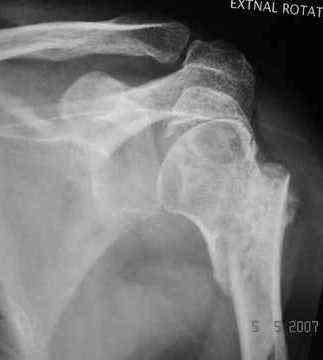

Dear all, A heavy built 30-year-old male patient sustained fracture dislocation of left shoulder about 8 months back.

For this ORIF with K-wires was done elsewhere. K-wires were removed at 6 weeks and patient advised physiotherapy. He has been doing physio dedicatedly since then.

He has 60* elevation…primarily it is scapulothoracic motion. External rotation at side is minus 30*.

Looking at his previous x-rays, I was thinking of refixing the greater tuberosity, however got anaxillary view done today which was never done during this period and this shows non-union.

It looks like the initial injury was a head splitting fracture. Presently the patient has a non-union at the level of the anatomical neck with displaced tuberosities. I would tackle the non-union, and would try to replace the tuberosities, a difficult procedure. I would use the proximal humerus locking plate from the AO.